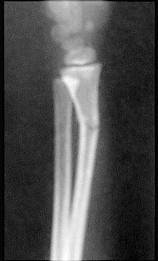

图示骨折(儿童青枝骨折)最主要体征是 ( )A、反常活动B、发热C、局部压痛与间接压痛D、骨擦音E、成角畸形

问题 图示骨折(儿童青枝骨折)最主要体征是 ( )

选项 A、反常活动 B、发热 C、局部压痛与间接压痛 D、骨擦音 E、成角畸形

答案 C